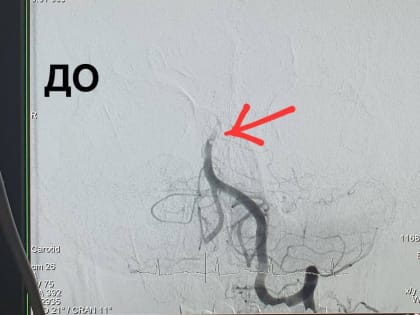

В Оренбурге хирурги удалили 59-летнему пациенту тромб в базилярной артерии мозга

В Оренбурге рентген-хирурги Алексей Демин и Эдуард Гаврилов удалили 59-летнему пациенту тромб в базилярной артерии мозга.

Рентгенхирурги Оренбурга впервые удалили тромбы из артерии головного мозга

Рентгенхирурги Оренбурга впервые провели операцию по удалению тромбов из базилярной артерии Евгения Богданова Фото: Оренбургская областная клиническая больница имени В.И.